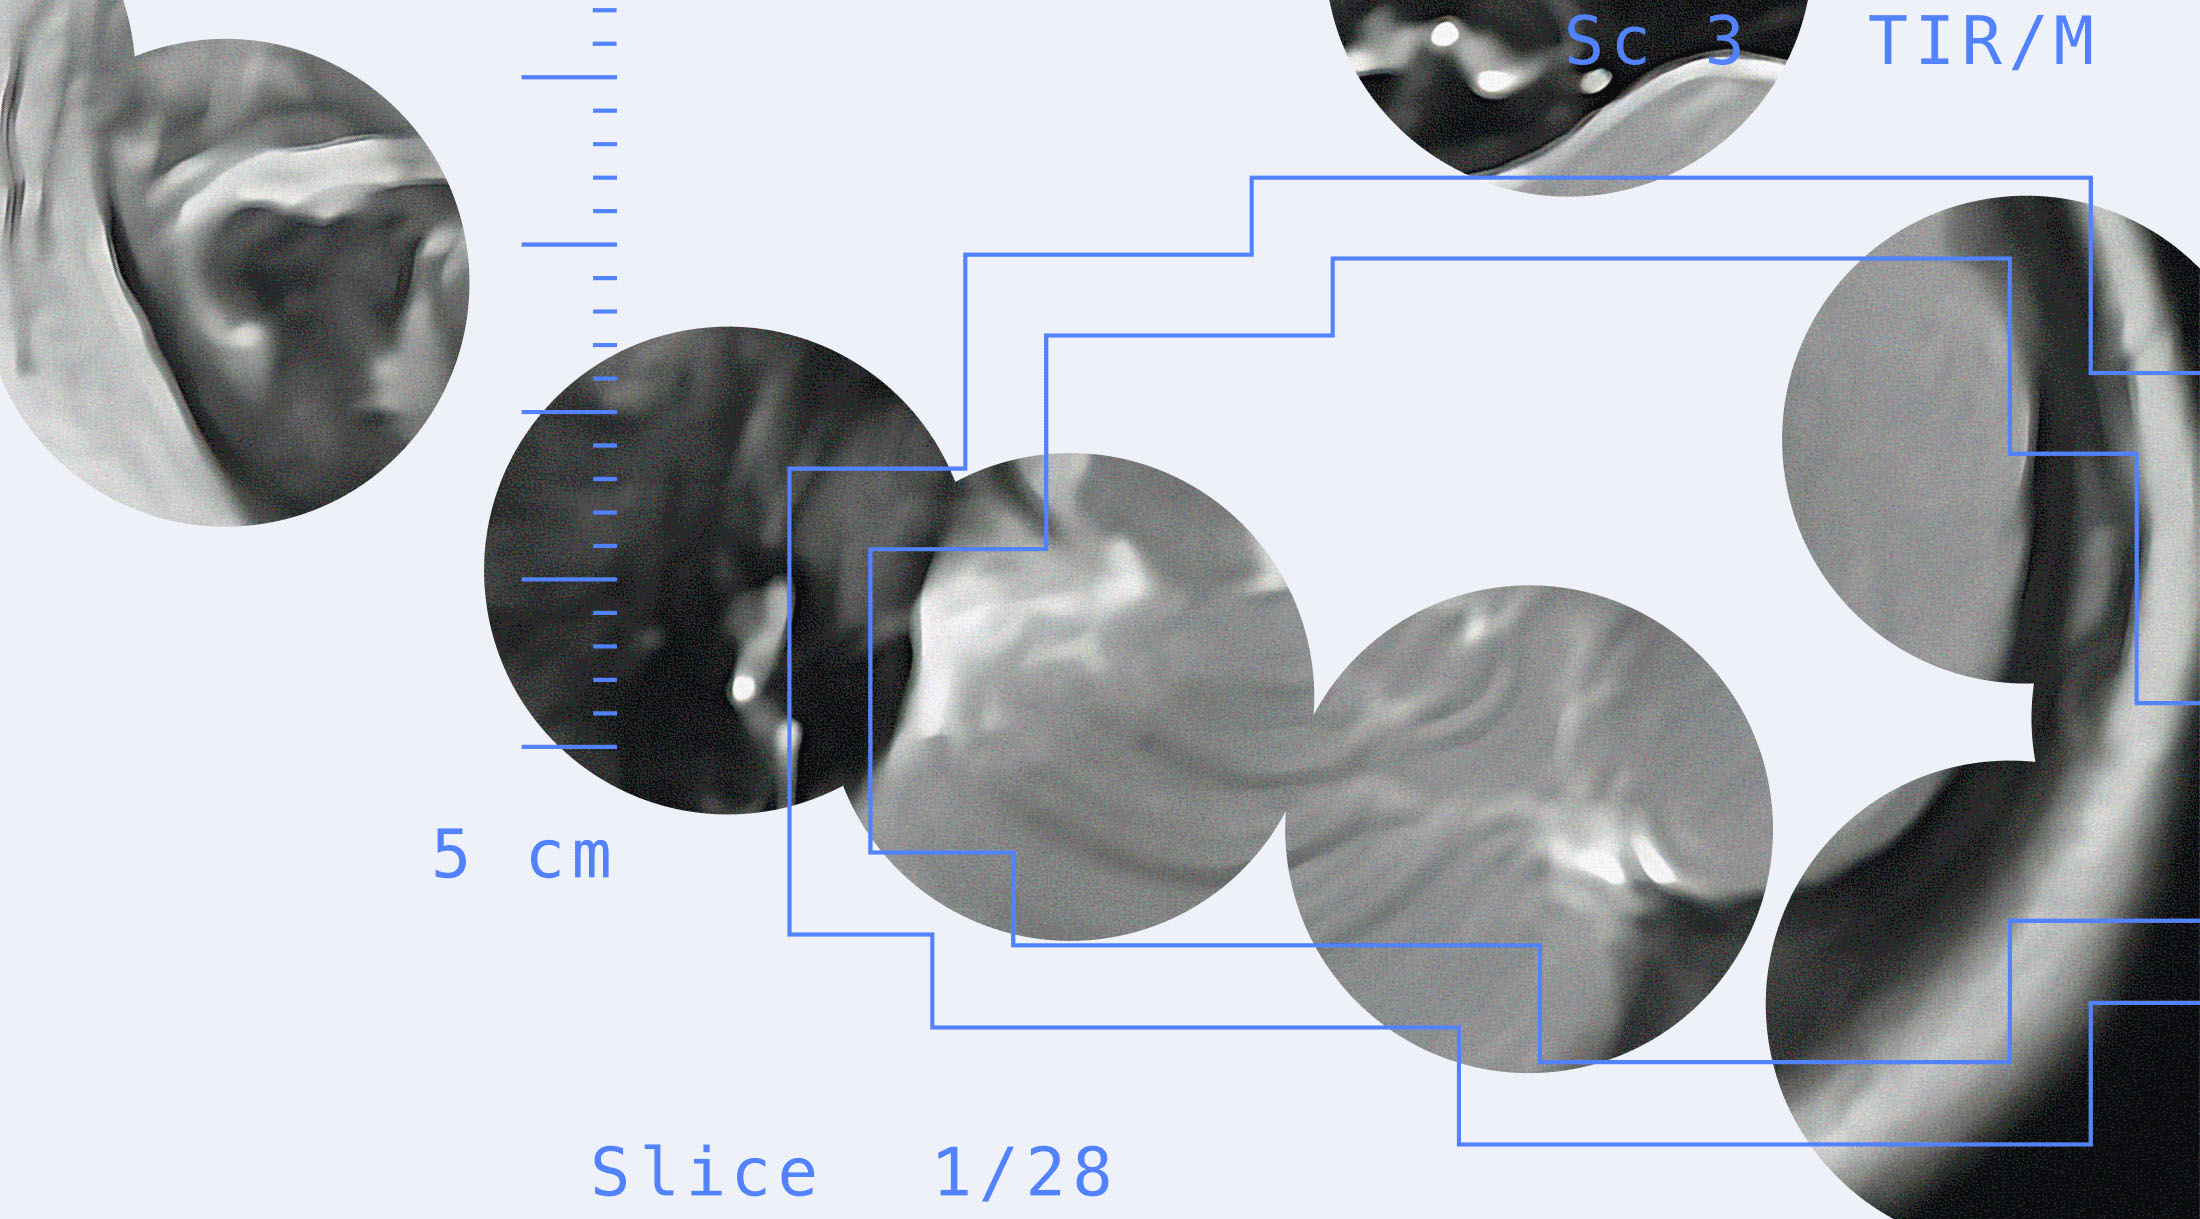

Решение представляет собой сервис, развёрнутый на платформе Yandex Cloud. Любой врач может использовать его бесплатно на специальной странице проекта. Специалист лучевой диагностики загружает в него результаты МРТ младенца. Данные анонимизируются — скрываются имя и фамилия пациента и другая конфиденциальная информация. Система с точностью свыше 90% выдаёт изображение с очерченными контурами и процентным соотношением серого и белого вещества в мозге ребёнка.

Новую систему разработали специалисты Центра технологий для общества платформы Yandex Cloud (входит в бизнес-группу Yandex B2B Tech) и студенты ШАДа, совместно с СПбГПМУ. Эксперты обучили нейросеть на 1,5 тыс. обезличенных МРТ-снимков пациентов университета и на открытом наборе данных, предоставленном в рамках международного конкурса по сегментации МРТ-изображений головного мозга младенцев MICCAI Grand Challenge. Для автоматической разметки применялась модель BIBSNet (Baby Intensity-Based Segmentation Network). Для сегментации изображений применили две нейросети: ResNet и U-Net. Специалисты Yandex Cloud предложили архитектуру решения, протестировали и настроили веб-сервис. Позднее разработку планируют выложить в открытый доступ, чтобы её могли использовать в медицинских и других проектах по всему миру.